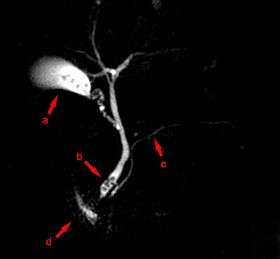

MRCP image showing stones in the distal common bile duct: (a) Gallbladder with stones, (b) Stones in bile duct, (c) Pancreatic duct, (d) Duodenum.

Magnetic resonance cholangiopancreatography (MRCP) is a medical imaging technique that uses magnetic resonance imaging to visualize the biliary and pancreatic ducts in a non-invasive manner.[1] This procedure can be used to determine if gallstones are lodged in any of the ducts surrounding the gallbladder.